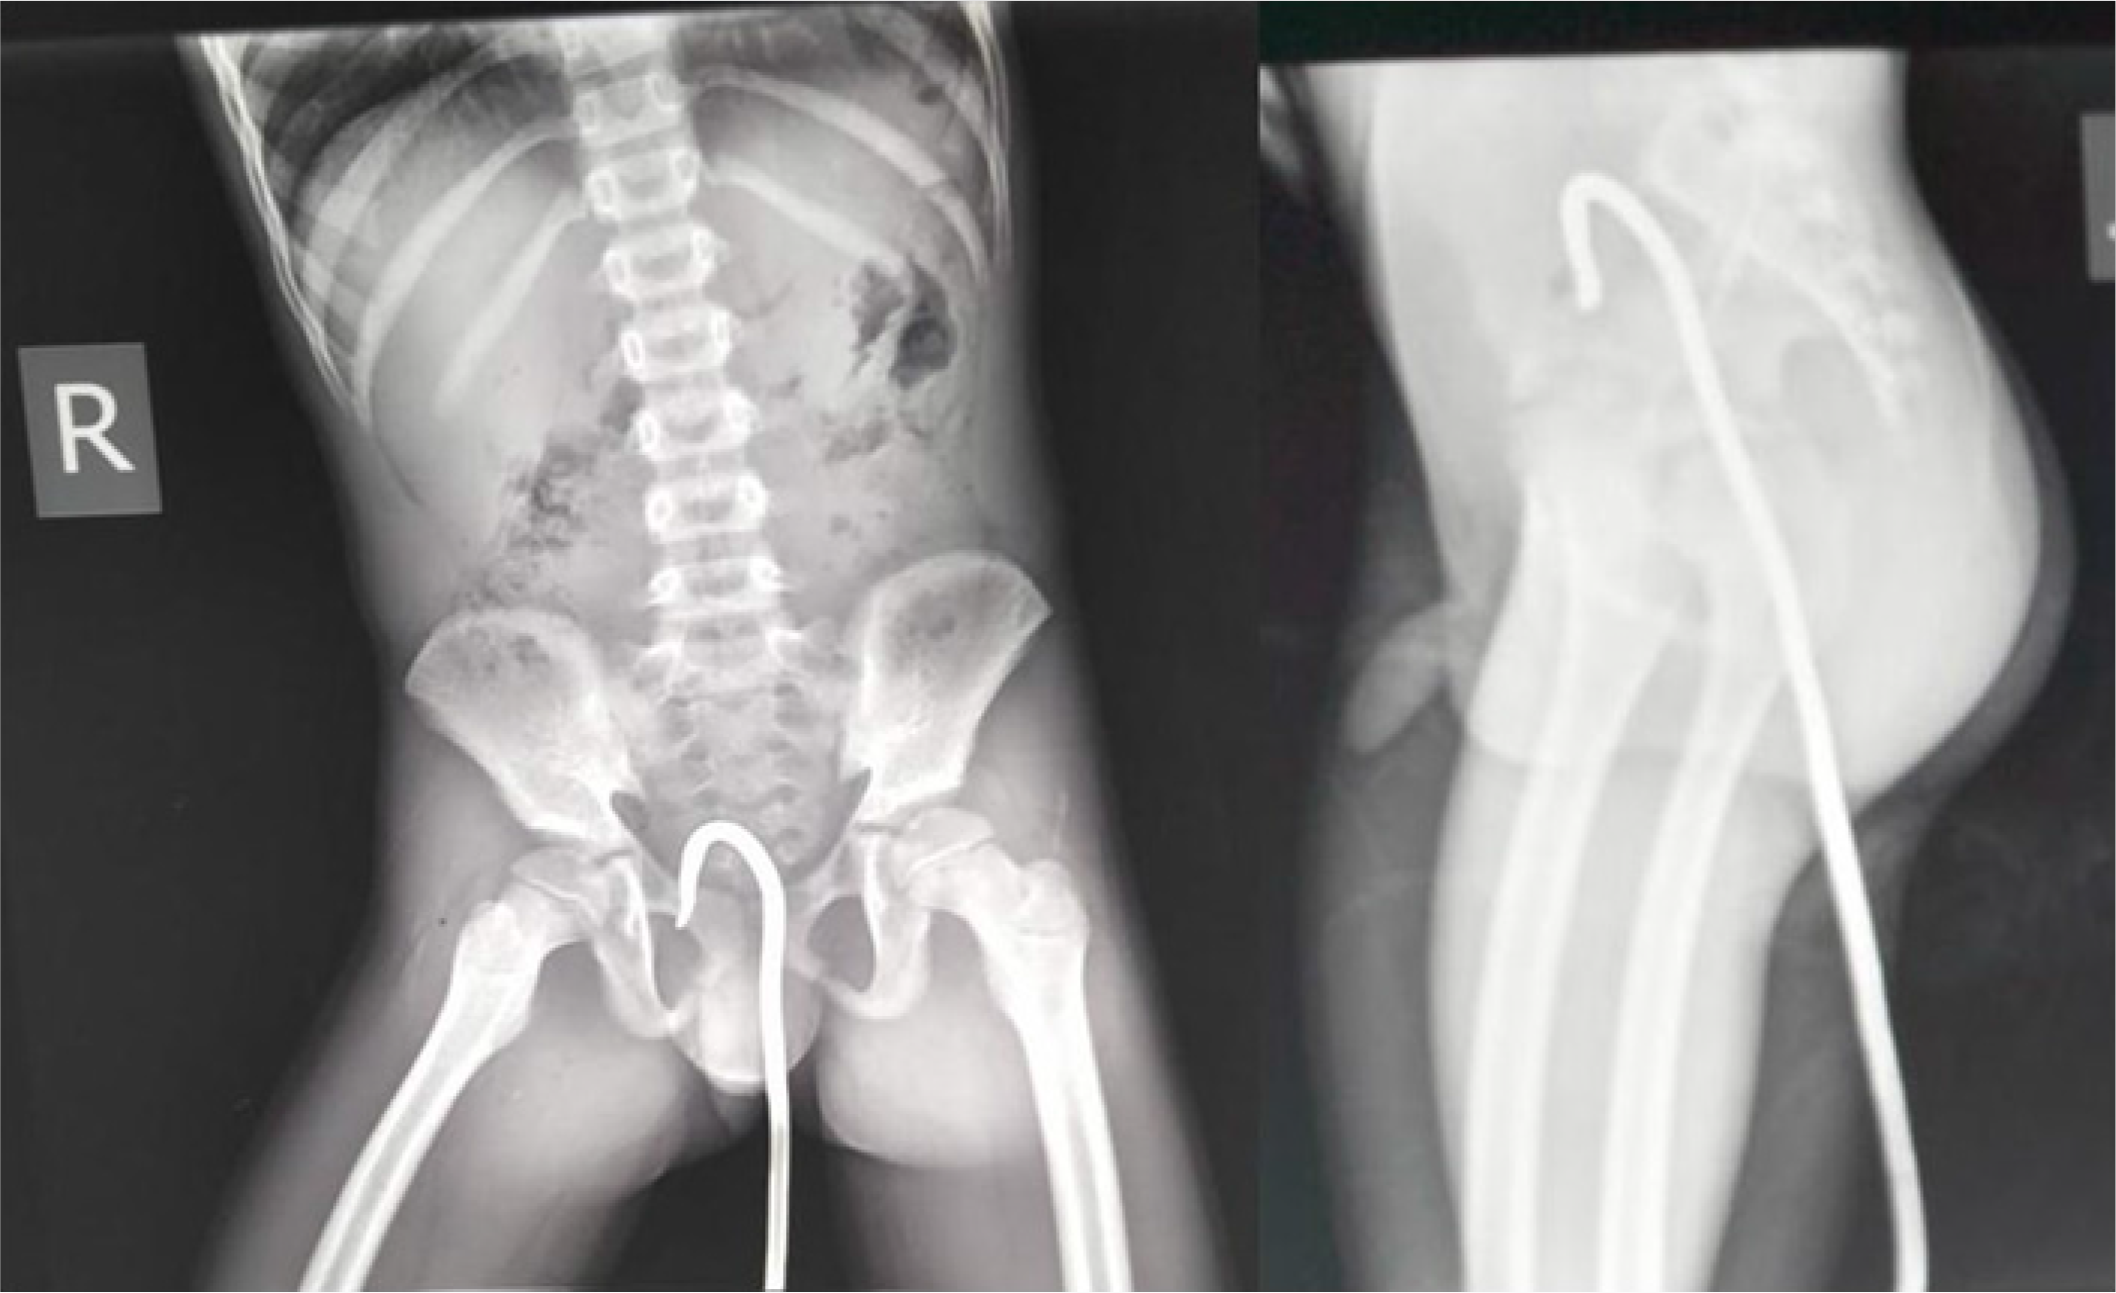

We present a case of an eleven-year old school boy slid and fell on an iron rod that penetrated his rectum through his anal canal. Presented with clinical features of peritonitis, where emergency laparotomy was done and the iron rod was extracted abdominally with primary repair of the rectum. The boy recovered well and was discharged four days after with no complications.